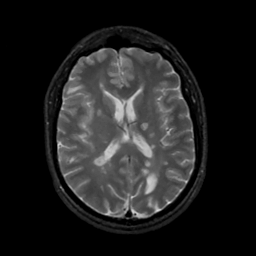

MR Study #6, March 17, 1991 -- Slice #29

[Home][Help][Clinical][Tour 1][Tour 2] Slice 29